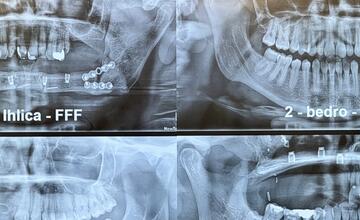

Pacientom, ktorí podstúpia náhradu čeľuste a sánky, sa vykonáva zákrok z ich vlastného kostného tkaniva z inej časti tela. Väčšinou je to lopatka, bedro alebo ihlica predkolenia